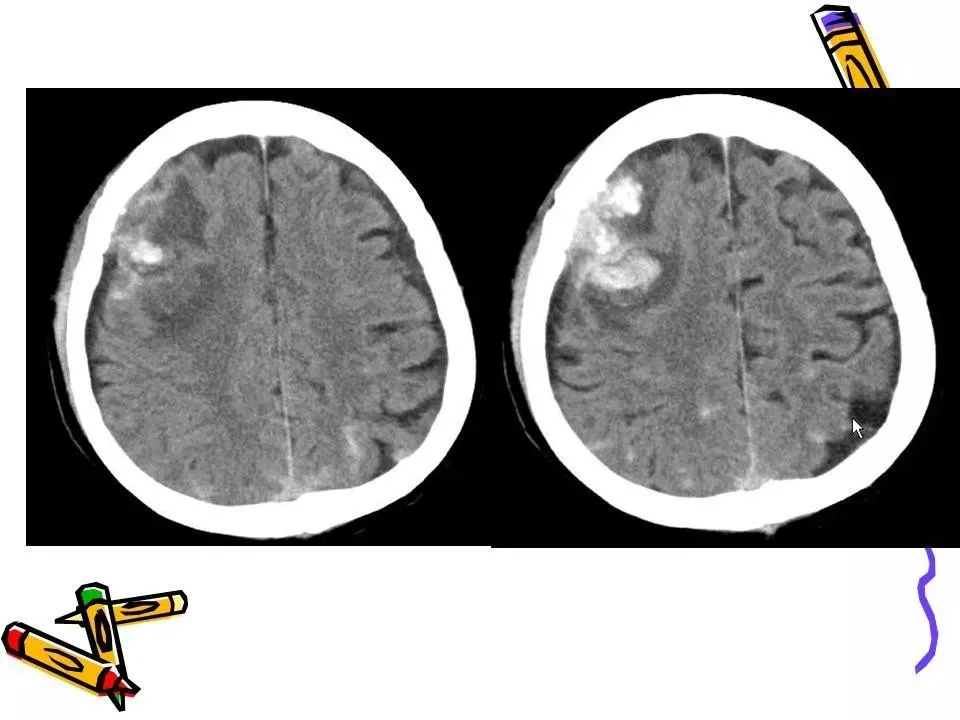

>常见颅脑外伤CT诊断(PPT)

常见颅脑外伤CT诊断(PPT)